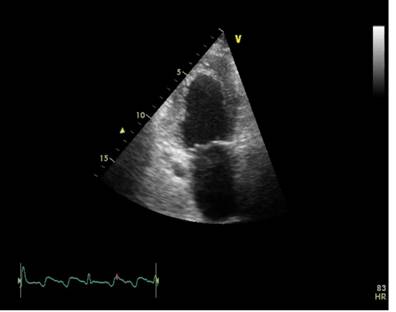

Ecocardiografie : evidentiaza ventricul stang cu dimensiuni la limita superioara a normalului cu disfunctie sistolica severa de ventricul stang (FEVS 30%), prezentand hipokinezie difuza pe peretii VS, dilatare usoara de Ao asc ( 44mm), hipertensiune pulmonara moderata- PAP sistolica 55 mmHg.(Fig. 3, 4,5).

Fig. 3 Sectiune apicala doua camere, hipokinezie pereti VS anterior si inferior. Fisier hera 32 movie